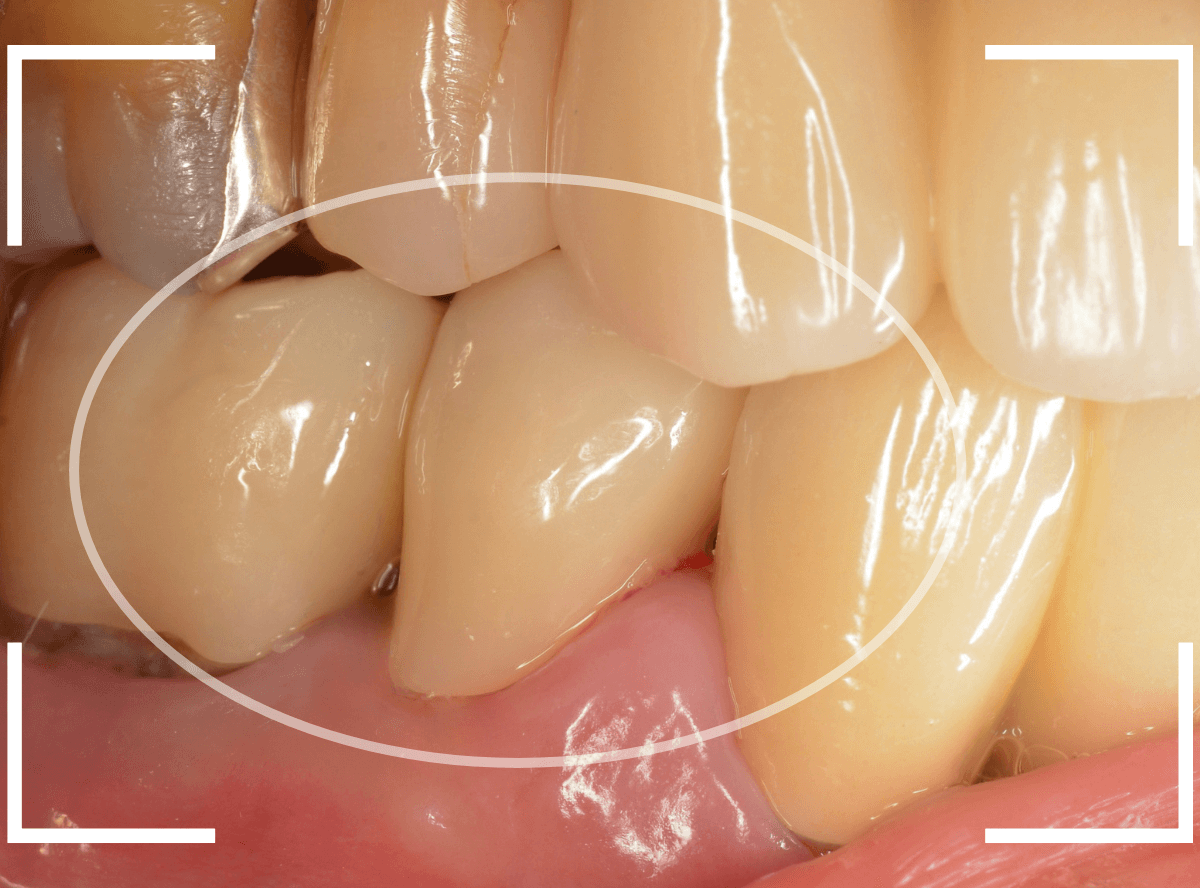

治療前のCAD/CAM冠と、ジルコニア・クラウンの比較です。

CAD/CAM冠も見た目は白いですが、人工物っぽさが大きいのがわかると思います。

また、ジルコニアに比べると素材が脆弱で、長持ちさせるのは難しいです。

さし歯の治療を受ける際は、素材のメリット・デメリットをよく理解した上で選んでいただければと思います。